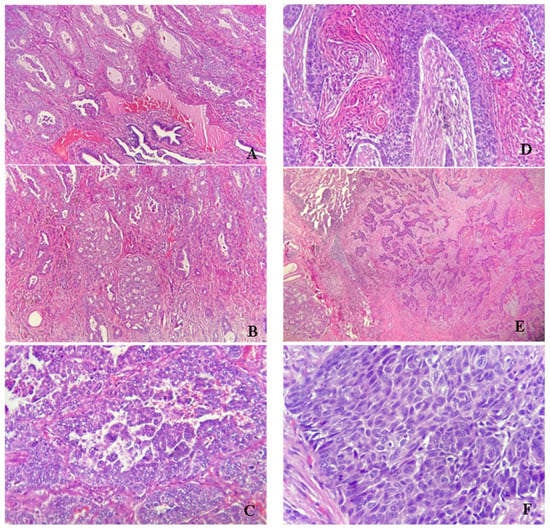

- Analysis of clinical data of patients diagnosed with primary lung malignancies; the patient’s ages, sex, and domicile were quantified to identify a correlation between pollutants and histological forms of cancer. The diagnosed tissue specimens came from the thoracic Surgery Clinic of the Brasov Military Hospital’s surgery rooms and the Pneumoftiziology Clinic of the Respiratory Diseases Hospital Brasov. Thus, tumorectomies, lung specimens (lobes, segments), endobronchial biopsies, pleural fluids, aspirates, and bronchial lavages were diagnosed. The histopathological specimens were subjected to pathological processing techniques (fixation in 10% buffered formalin, dehydration, and paraffin impregnation by automatic processing, sectioning, staining of sections by hematoxylin-eosin stain. The examined liquids were centrifuged, the sediment being examined both directly and in Papanicolaou and Giemsa staining, and by inclusion in paraffin, in the form of a cytoblock prepared with neutral proteins. For histological confirmation of the microscopic diagnosis, immunohistochemistry was performed, using the panel of mom and polyclonal antibodies specific to primary lung malignancies (TTF1 clone SP141, Napsin A clone MRQ-60, anti-p40 clone BC28, Anti-Pan Keratin clone AE1/AE3/PCK26). Immunohistochemistry was performed automatically using Benchmark Ventana Gx equipment. The microscopic study was performed using a Zeiss Primo Star microscope and capturing images from the paper was performed using an AxioCam 105 color microscopy camera. The Pathology Department owns the medical equipment. To establish the post-surgical treatment, some specimens, depending on the tumor stage, were investigated by molecular biology techniques to develop the prognostic factors.